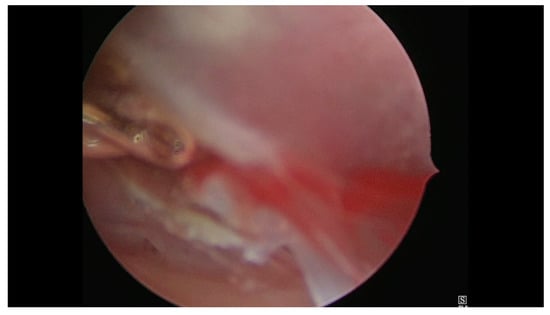

- Case 1. Hysteroscopy was performed in two steps. During the first phase a 5 mm Bettocchi hysteroscope (Storz®, Karl Storz SE & Co, Tuttlingen, Germany) with 5 Fr bipolar electrode Versapoint Twizzle (Gynecare®) was used to identify the GS: it was opened and the pregnancy terminated by cord section and vessels were partially coagulated; subsequently, the cervix was dilated and we performed a resectoscopy. During the second phase the GS and the embryo were removed and a 10 mm resectoscope with bipolar Versapoint (Gynecare®) was used to obtain a complete resection of the residual chorial villi. Lastly, we performed an electrocoagulation of the bleeding vessels on implantation site, in order to control the hemostasis (Figure 1, Figure 2, Figure 3 and Figure 4)